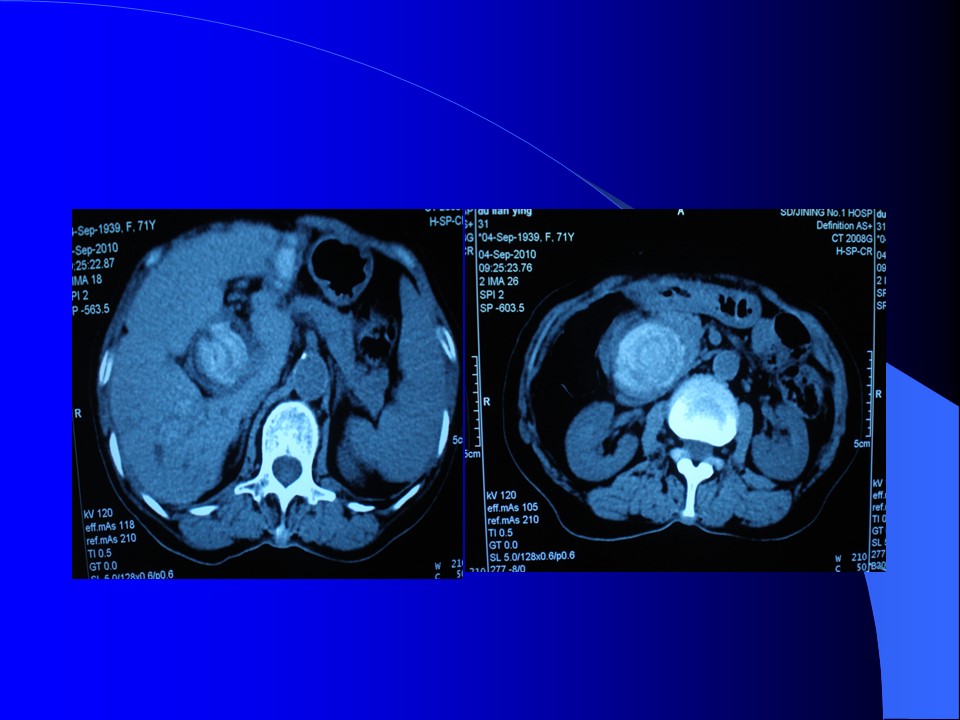

胆道系统包括肝内、外胆管,胆囊及Oddi括约肌等部分。

长约7~9cm,直径0.6~0.8cm。直径超过1cm,应视为病理情况。